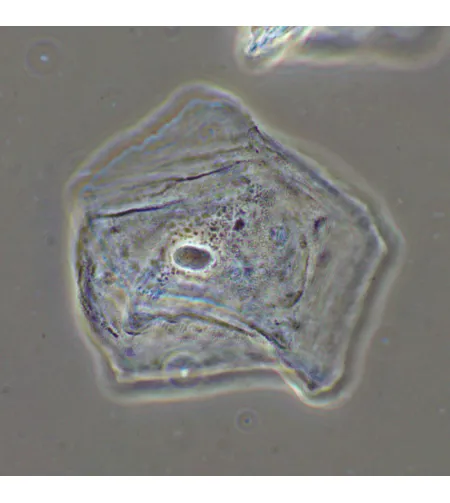

MAGUS SPH2 faasikontrastsuseadme koosneb faasikontrasti liugurite komplektist, faasikohustusega andurite komplektist ning keskendava teleskoobist. Faasikontrastsuseadet kasutatakse läbipaistvate madala kontrastsusega proovide uurimiseks, mis pole heledas väljavalguses nähtavad. Värvimine tapab elusaid rakke. Tehnika peamine eelis on see, et seda saab kasutada elusate värvimata organismide uurimiseks nende loomulikus olekus. Tehnikat kasutatakse meditsiinis, ökoloogias, farmakoloogias, põllumajanduses jne.

Faasiobjektiivid erinevad tavalistest objektiividest selle poolest, et nende väljumispupilli tasapinnal on faasiring. Tasapinnelised akromaatilised faasiobjektiivid moodustavad pilti, mille fookus on keskel ja servadel sama, seega on moonutus ebaoluline. Kroomaatilised aberratsioonid on parandatud siniste ja punaste jaoks, sfäärilised aberratsioonid - roheliste jaoks ning väli kõverus on parandatud 90% vaatevälja läbimõõdu jaoks. 10x objektiivi kasutatakse proovide uurimiseks koos kaanega või ilma. 20x, 40x ja 100x objektiive kasutatakse proovide vaatlemiseks 0,17mm kattega. 100x objektiiv toetab õli immersiooni. Objektiivid on mõeldud lõpmatu korrektsiooniga torupikkuseks. Parfokaalne kaugus on 60mm.